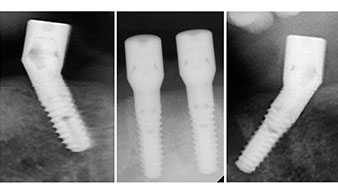

Zur Planung und Risikominimierung wurde eine dreidimensionale Volumentomografie (DVT, Planmeca) erstellt. Dieses zeigte, dass die Qualität und Quantität des Knochens für eine Operation und Sofortversorgung nach der Fast & Fixed-Methode ausreichend war. Nach Protokoll dieses Konzeptes wird in Regio 35, 32, 42 und 45 implantiert. Durch die bis zu 45-Grad-Schiefstellung der distalen Implantate wird das Durchtrittsprofil nach posterior verlegt und ein größeres Stützpolygon erreicht (Abb. 3).

Das chirurgische Protokoll der verwendeten Implantate (SKY, bredent medical) schreibt eine Umdrehungszahl von 1.200/min für die Pilotbohrungen vor (Abb. 7–9).

Dies entspricht der nächsten Position der Voreinstellung am Implantmed. Zu erkennen ist die etwa 45-Grad-Schräghaltung des W&H Winkelstückes nach mesiokaudal in Regio 45, um den Nervus mentalis zu schonen. Das Foramen mentale gilt als anatomische Orientierung für alle Bohrungen in diesem Bereich. Die anschließenden Bohrungen werden mit einer reduzierten Umdrehungszahl von 300/min durchgeführt (Abb. 10 und 11).